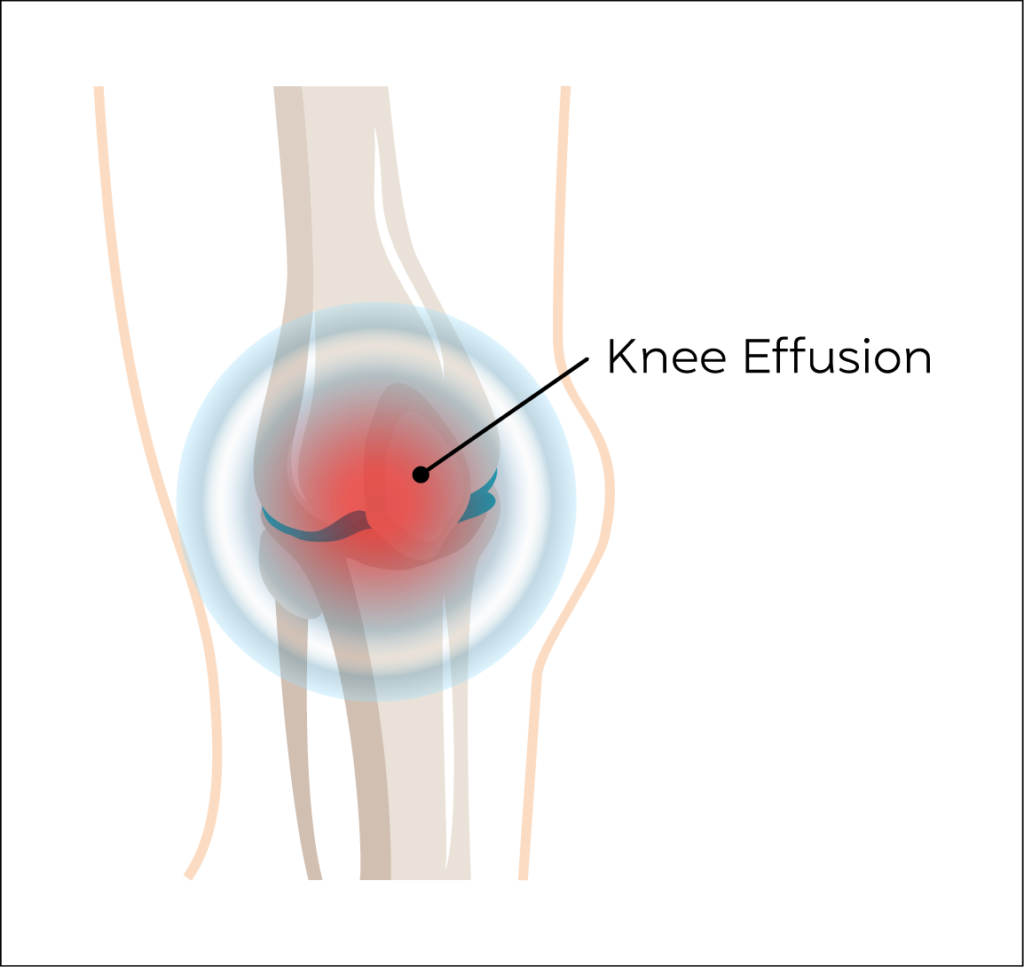

Knee Effusion

Knee joint Effusion is when excess fluid accumulates in or around the knee joint. A normal average knee joint has 4-6 mls of synovial fluid. It can result from both trauma and non-traumatic causes such as inflammation.

It is a relatively common condition.

The main symptoms of knee effusion are swelling and redness of the skin around the kneecap, stiffness in the joint and difficulty straightening or putting weight on the knee, alongside a pain.

Ultrasound can measure the extent of an effusion and can be used to drain the fluid using a needle followed by an injection of steroids to help prevent recurrence especially in inflammatory conditions.